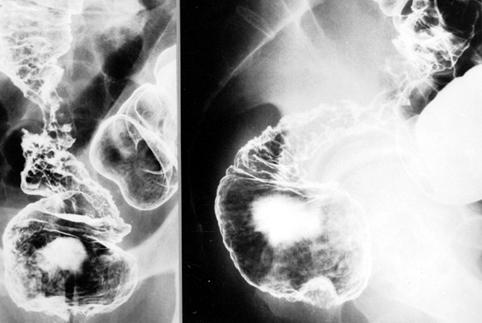

Type 4 (diffusely infiltrating type) advanced colon cancer with giant holds and long segmental stenosis from the rectum to the sigmoid colon mimicking an inflammatory stenotic lesion.

Malignant epithelial tumor/Adenocarcinoma

Large intestine(Colon)/Rectum

X-ray

Type 4 Diffusely infiltrating type/

40 -

serosa (adventitia)